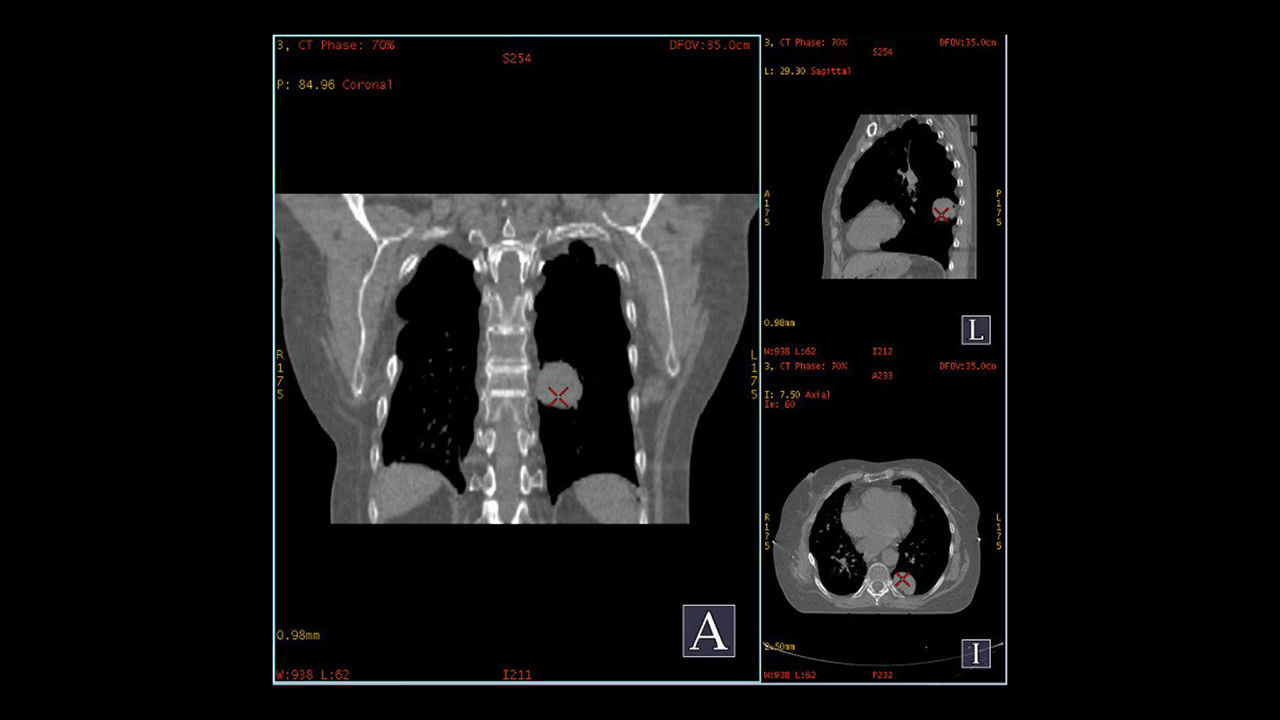

Automate Cardiac CT post processing and streamline your workflow.

<p>SnapShot Freeze 2</p>

Learn more

<p>CardIQ Xpress 2.0 Reveal</p>

<p>SmartScore 4.0</p>